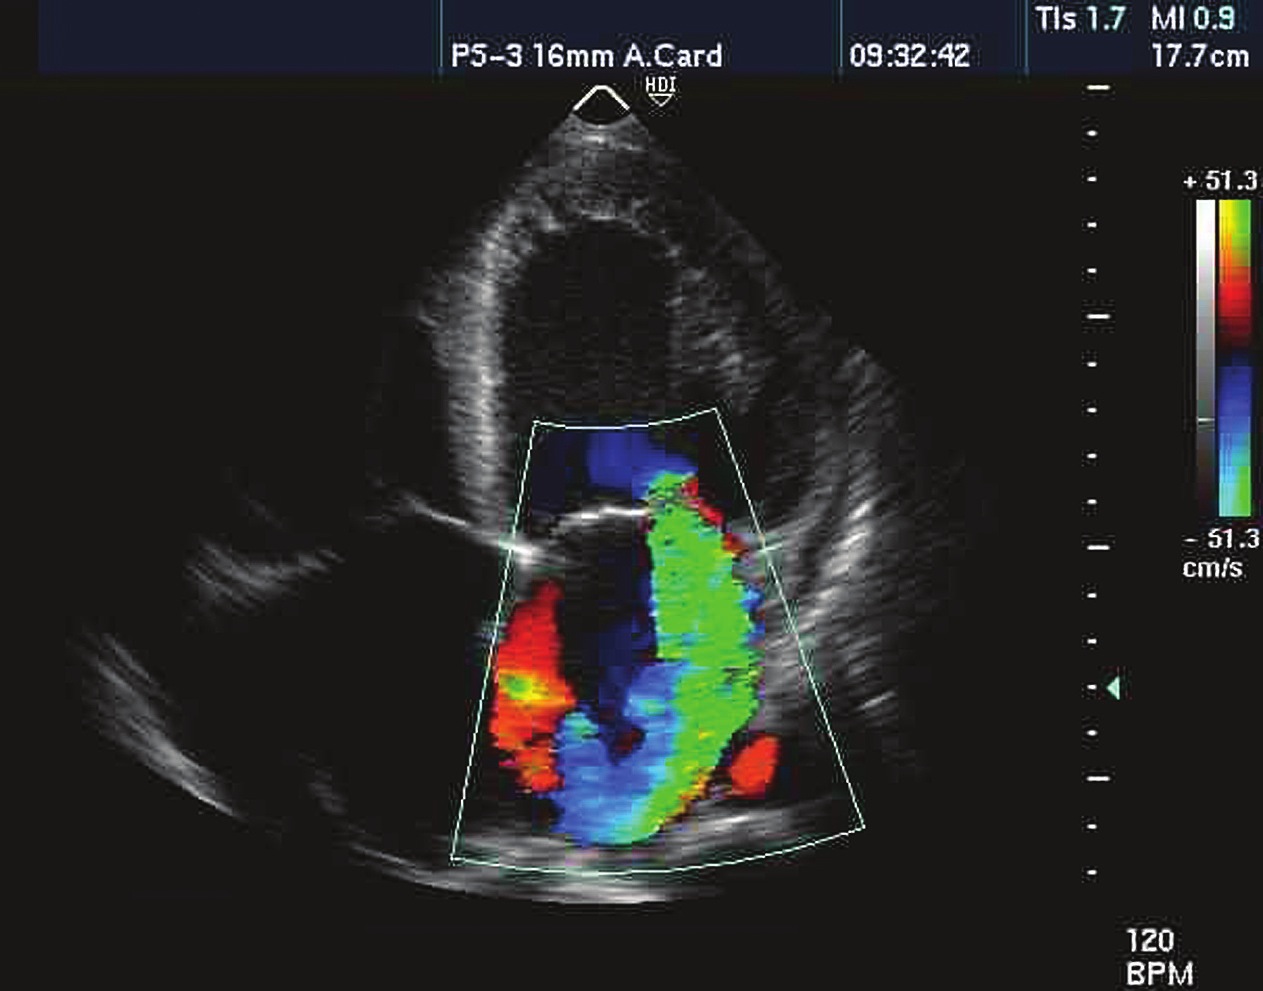

Del mismo modo, la cuantificación del grado de reflujo mitral se puede realizar a través del análisis de una serie de variables (Figura 6):

Figura 6 Insuficiencia mitral severa en ecocardiografía transtorácica.